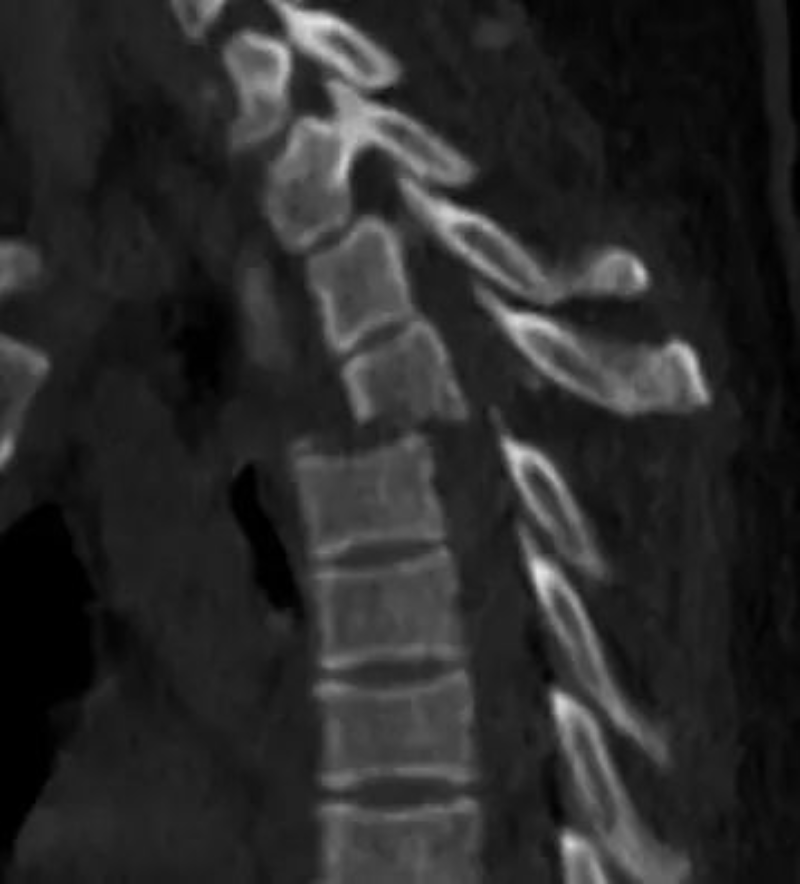

△ 術后復查見骨折脫位復位良好,內固定在位。